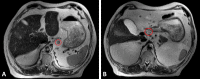

Accurate preoperative staging of gastric cancer and the assessment of tumor response to neoadjuvant treatment is of importance for treatment and prognosis. Current imaging techniques, mainly endoscopic ultrasonography (EUS), computed tomography (CT) and 18F-fluorodeoxyglucose positron emission tomography (18F-FDG PET), have their limitations. Historically, the role of magnetic resonance imaging (MRI) in gastric cancer has been limited, but with the continuous technical improvements, MRI has become a more potent imaging technique for gastrointestinal malignancies. The accuracy of MRI for T- and N-staging of gastric cancer is similar to EUS and CT, making MRI a suitable alternative to other imaging strategies. There is limited evidence on the performance of MRI for M-staging of gastric cancer specifically, but MRI is widely used for diagnosing liver metastases and shows potential for diagnosing peritoneal seeding. Recent pilot studies showed that treatment response assessment as well as detection of lymph node metastases and systemic disease might benefit from functional MRI (e.g. diffusion weighted imaging and dynamic contrast enhancement). Regarding treatment guidance, additional value of MRI might be expected from its role in better defining clinical target volumes and setup verification with MR-guided radiation treatment.